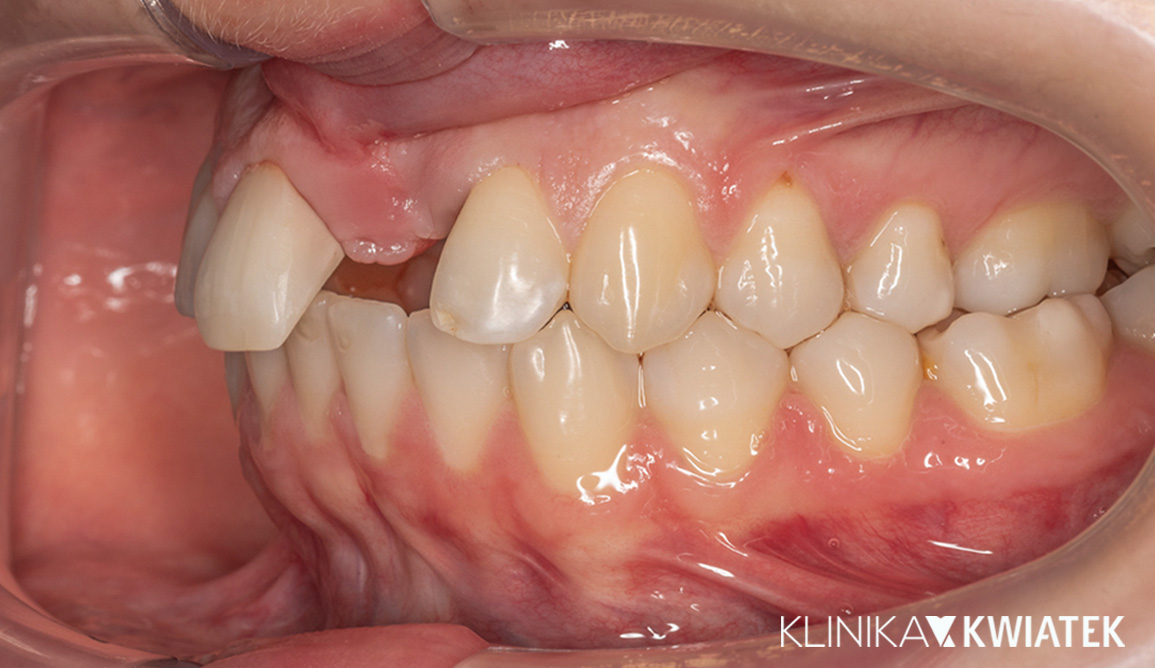

PRZED

PO

Pacjentka zgłosiła się z wadą zgryzu, licznymi ubytkami i utraconymi zębami trzonowymi, co powodowało trudności w żuciu i estetyczne niezadowolenie. Leczenie obejmowało ekstrakcje, ortodoncję, implantację oraz kompleksową rekonstrukcję protetyczną. Po kilkunastu miesiącach terapii Pacjentka odzyskała pełną funkcję zgryzu i piękny, harmonijny uśmiech.